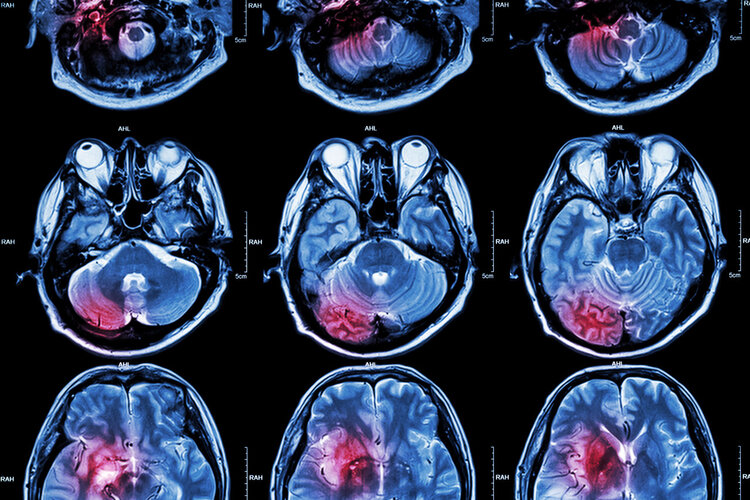

上了年纪的人 , 除了要警惕脑梗之外 , 还要警惕脑溢血 。 脑溢血也被称为是出血性脑卒中 , 一般是由于脑血管小动脉出现破裂 , 导致血液进入了脑组织引发的一系列症状 。

多数脑溢血的发生是因为患者大脑内部的小动脉出现了破裂 , 这也意味着动脉血管出现了粥样硬化 , 因为一般人正常的动脉血管是弹性比较大的很难破裂 , 而一旦出现了粥样硬化 , 血管就会变脆 。

一旦血压升高 , 就可能会导致血管壁破裂、出现脑溢血 , 甚至危及到人的生命安全 。